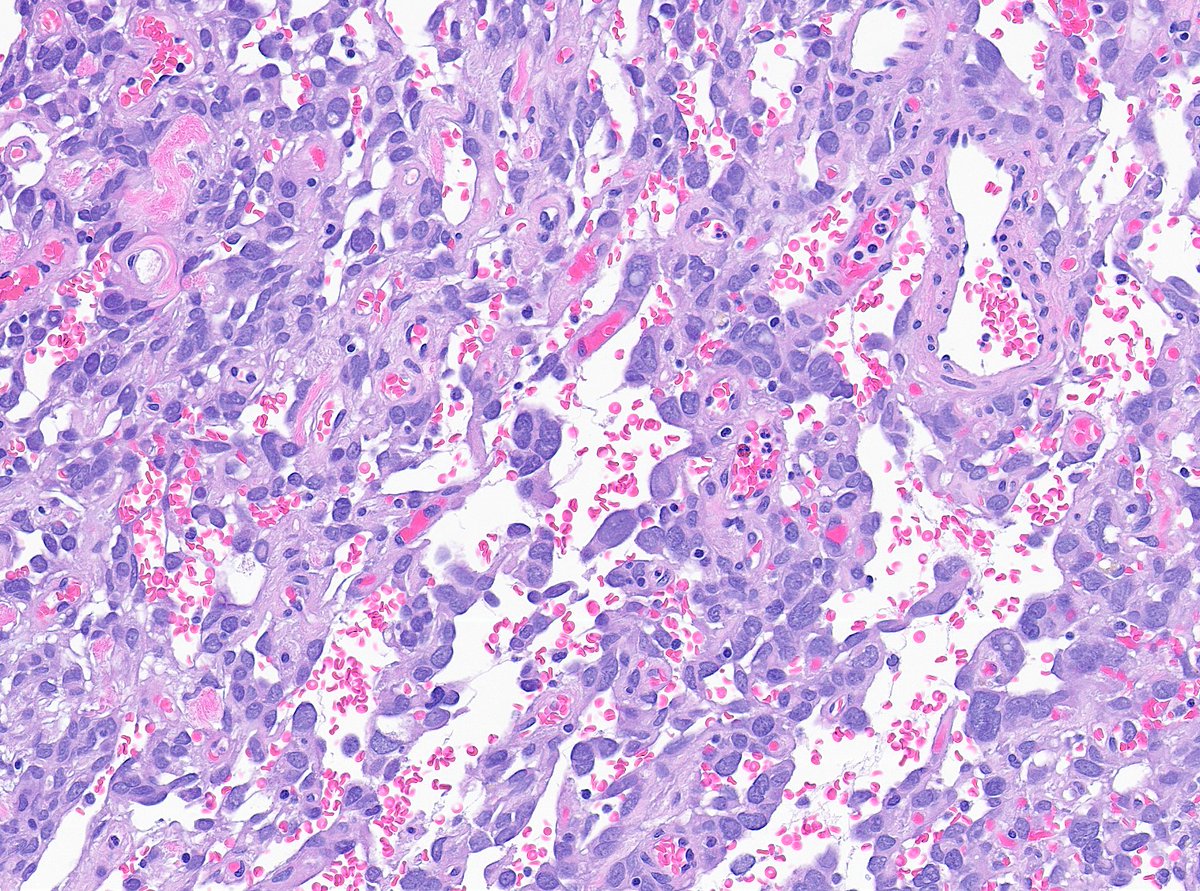

A very vascular tumor indeed - however the neoplastic cells are not endothelial. Here's a better look at another part of the same tumor:

What do you make of this tumor of the small bowel mesentery?🧐 #BSTpath #GIpath